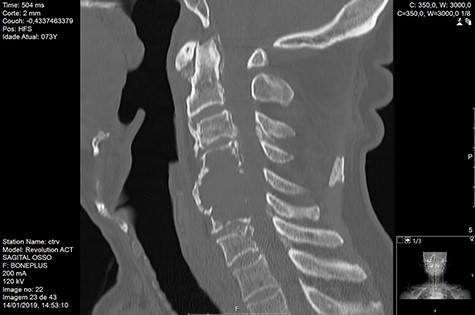

MRI and CT scans performed at 90 days post-radiation therapy showed an arrest of further progression of instability and resolution of the lytic lesion (Figs 7–13).

Computed tomography (CT) (Figs 1–3) and magnetic resonance imaging (MRI) (Figs 4–6) of the cervical spine were performed and revealed a lytic lesion involving most of C4, C5 and C6 vertebral bodies with bilateral extension to the posterior spinal elements of C4 and C5 and complete disruption of C4-C5 and C5-C6 intervertebral discs.

The Spinal Instability Neoplastic Score (SINS) [4, 6, 7] for assessing spinal instability from metastatic disease was used and the lesion was deemed unstable (SINS 13), with impending risk of increased neurological damage.